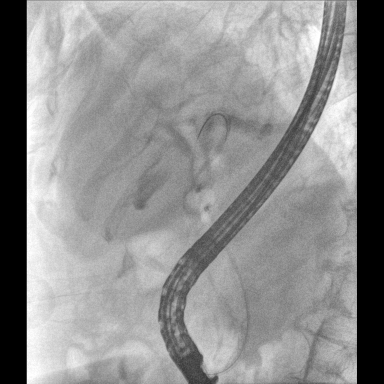

具備血管造影及數(shù)字減影(DSA)、路徑圖(Road-map)、透視、攝影等功能。 廣泛適用于介入科、血管外科、腫瘤科、消化內(nèi)科及骨科等多個臨床科室,典型應(yīng)用包括:TACE(肝腫瘤栓塞與化療灌注術(shù))、心臟起搏器置入術(shù)、四肢動脈造影術(shù)、下肢靜脈濾器置入術(shù)、ERCP(經(jīng)內(nèi)鏡逆行胰膽管造影術(shù))等。